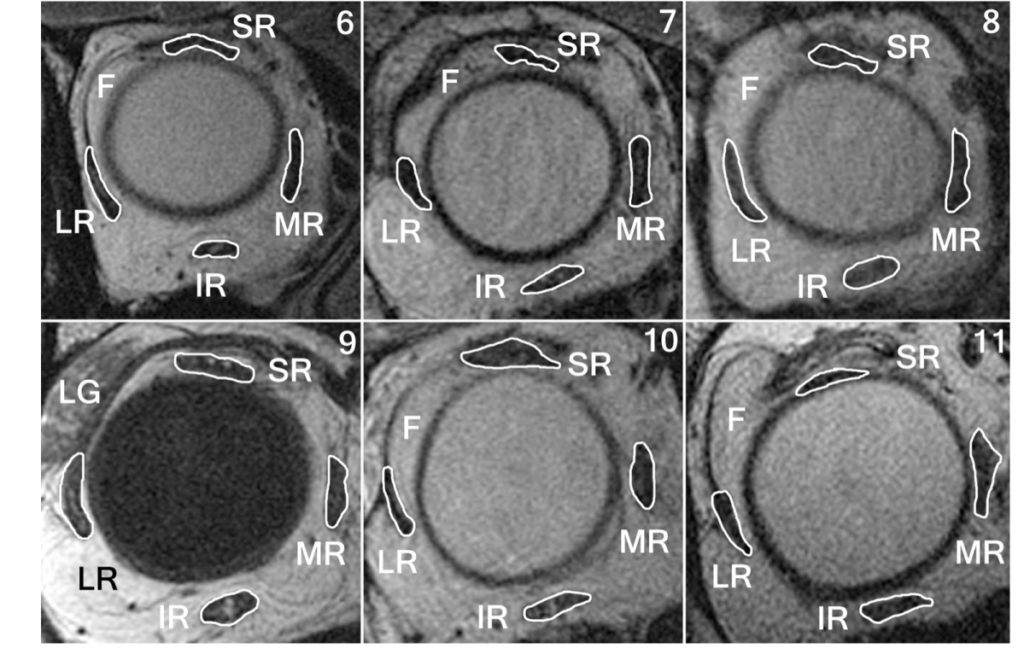

Confocal microscopy of a neuropathic cornea

Patient with corneal neuropathy from a refractive surgery 7 years…